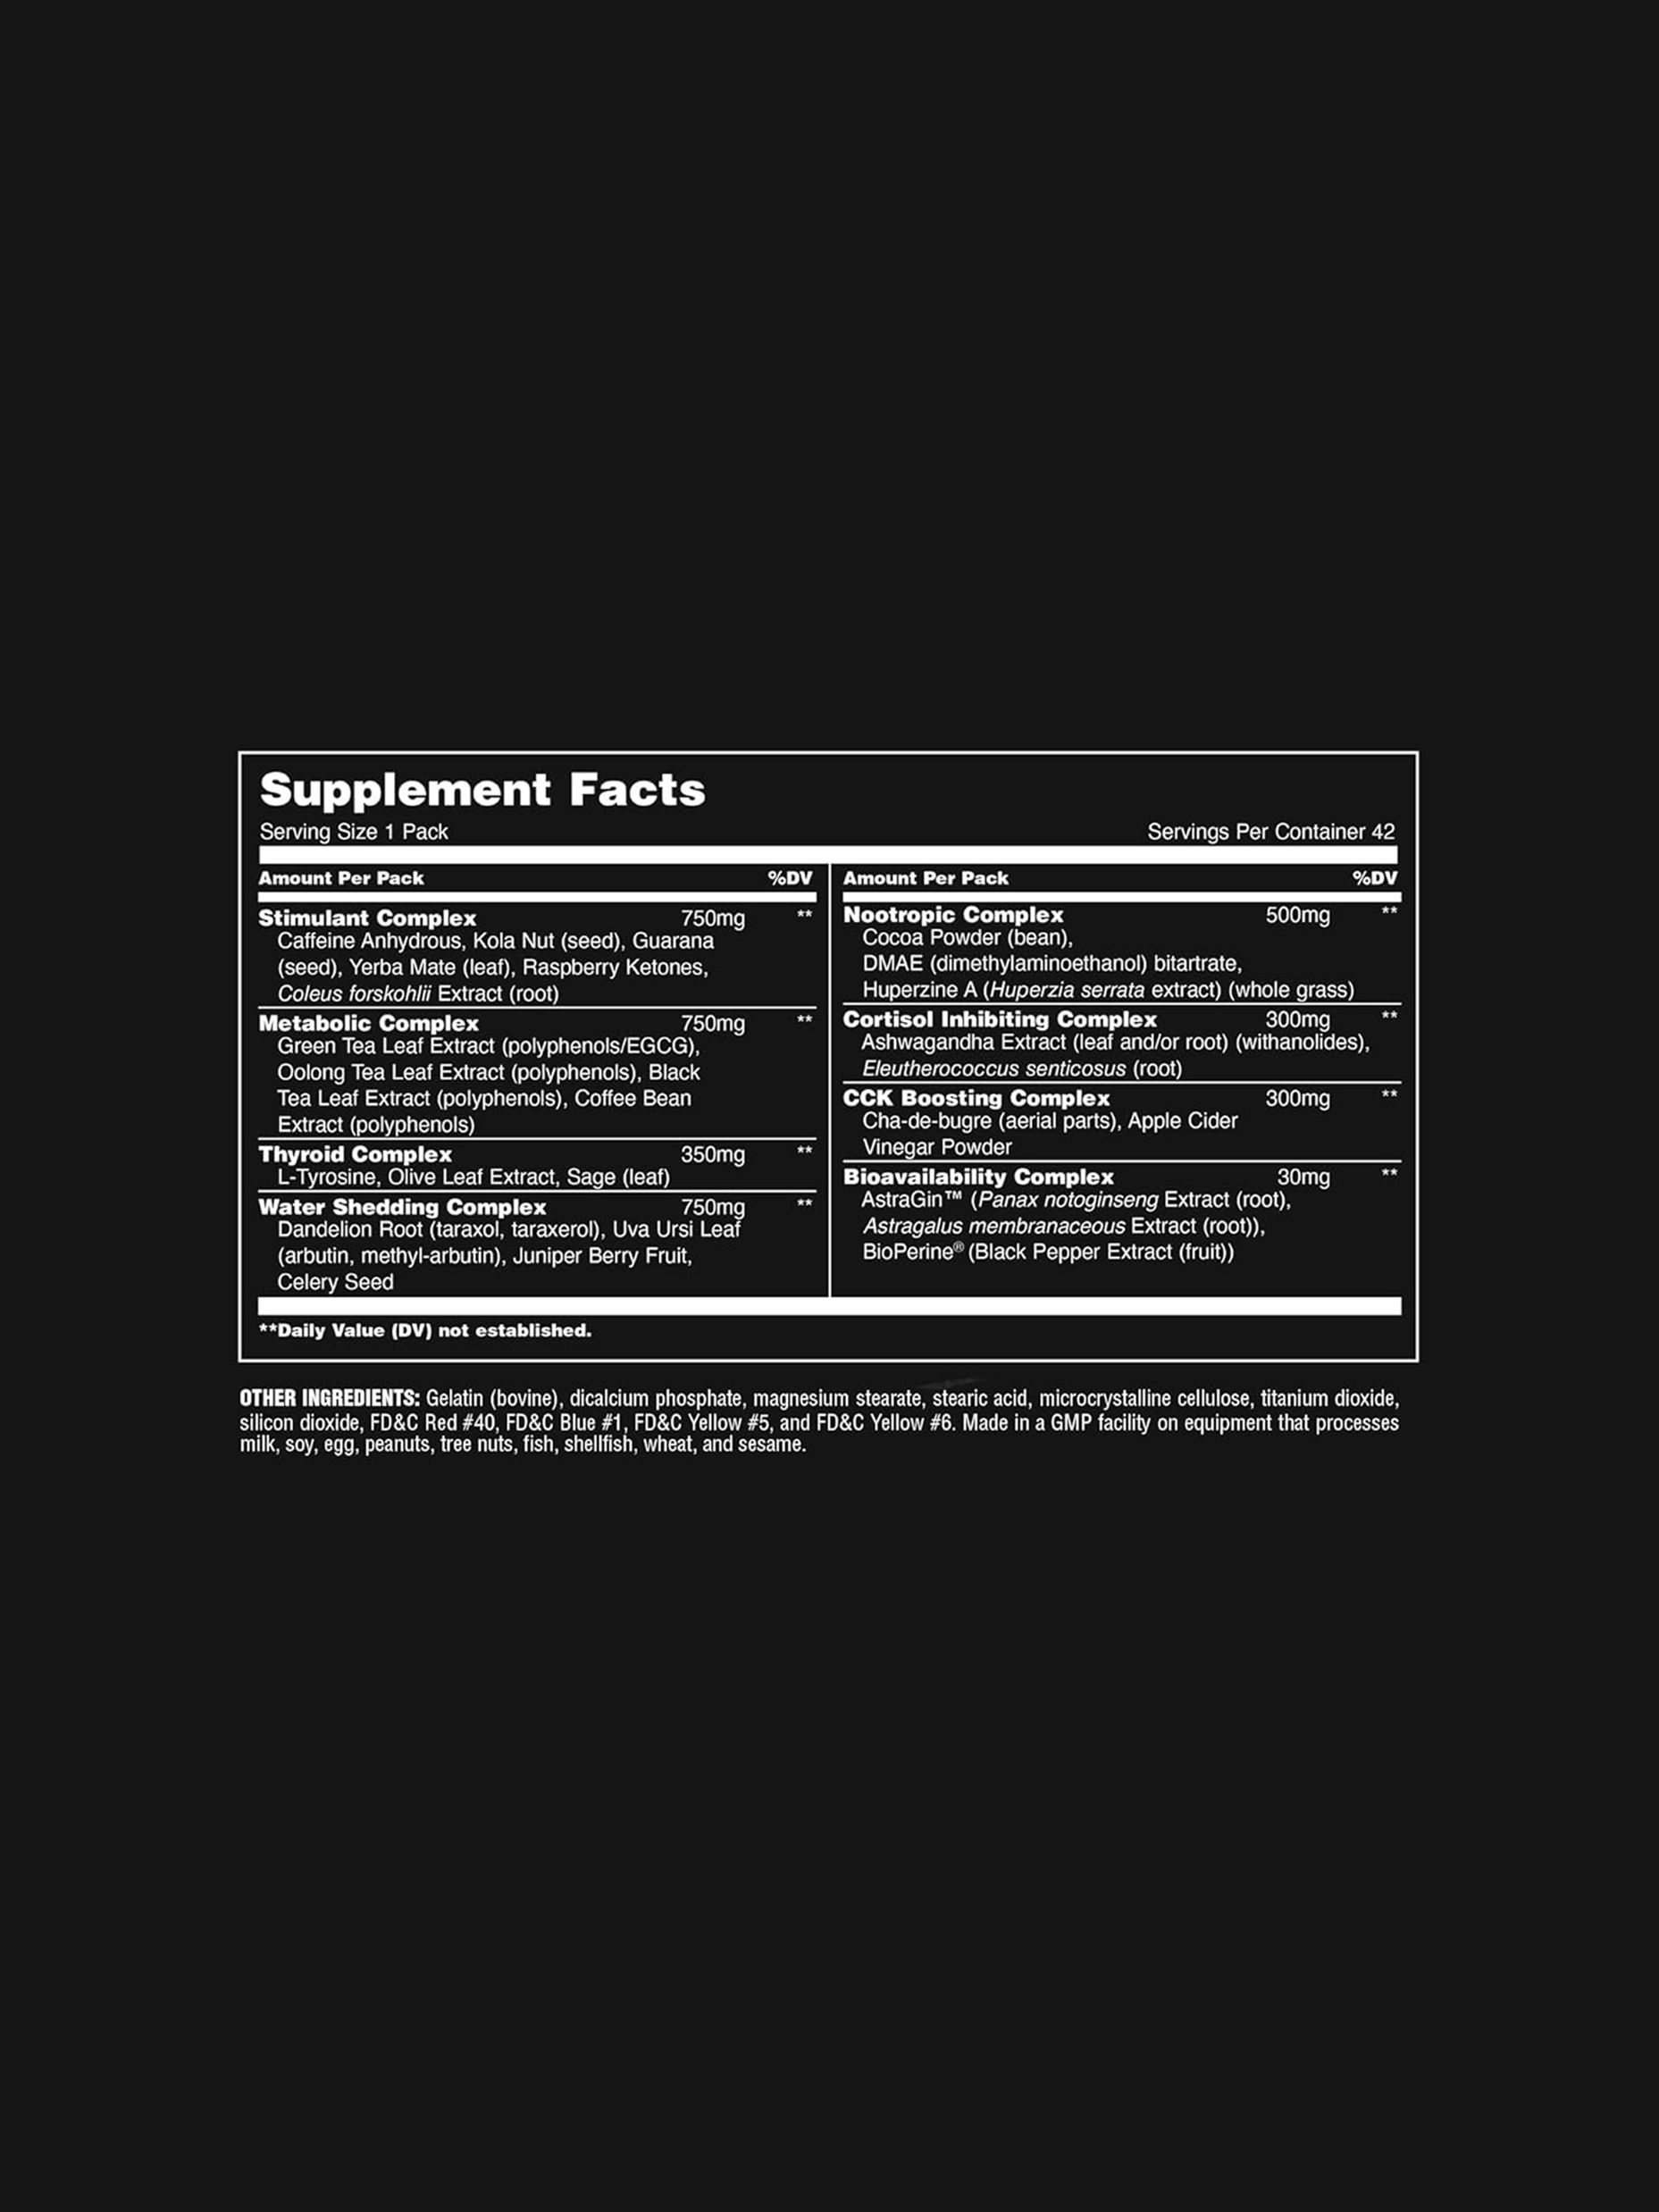

최강의 컷팅 제품 애니멀 컷이 인터내셔널 버전으로 돌아왔습니다. 기존에 한국 세관에 문제되었던 성분은 제거되고 문제가 되지 않는 최강의 성분으로 만들어진 애니멀 컷은 여러분의 체중조절에 확실한 만족감을 드릴 것입니다. 카페인 무수, 과라나 등 다양한 카페인 성분과 다양한 성분들이 기초 대사량을 높여 여러분의 체지방을 제거하고 더욱 멋진 몸으로 만들어 드립니다. -

2어떤 특징이 있나요?애니멀 컷은 신진대사와 기초대사량을 늘려 추가적으로 칼로리 감소가 되며 트레이닝에 조금 더 오랫동안 집중할 수 있도록 도와줍니다. 다이어트와 특히 컷팅 시에 필요한 모든 사항을 충족해 주는 제품입니다. 1패킷 안에 들어있는 엄청난 함량을 자랑하는 다양한 성분이 여러분의 다이어트와 체중조절에 기여하며 특히 대회를 준비하는 분들에겐 큰 도움이 될 것입니다.

3어떤 카페인들이 들어있나요?먼저 강력한 각성효과를 갖고 있는 카페인 무수를 비롯해 심리적인 안정에 영향을 주는 테오브로민을 함유한 콜라 나무 열매, 다른 어떤 식물보다 더 많은 카페인을 함유하고 있고 에너지와 경각심을 증가시키는 것을 포함하여 다양한 작용을 하는 과라나, 남미 전통 음료로 산화 방지제가 많고 차나 커피와 비슷한 천연 카페인을 함유하고 있는 예르바메이트와 러시아와 중국에서 수천 년 동안 전통 의학에 사용된 식물 신체적 지구력을 향상시키고, 에너지를 증가시키며, 피로를 줄이기 위해 사용되는 시베리아 인삼 파우더가 함유되어 있습니다.

4다른 성분들은 어떤가요?애니멀 컷은 카페인 뿐만 아니라 28가지의 다양한 성분들을 갖고 있습니다. 아쉬와간다, 우롱차 추출물, 녹차 추출물, 커피 추출물, 민들레 파우더, 쐐기풀 추출물 등 자연에서 나온 다양한 성분들이 여기에 들어있으며 4500mg 넘는 컷팅 복합체를 함유하고 있습니다. 이 성분들은 신진대사율을 증가 시킴과 동시에 갑상샘 자극하고, 기초대사율 증가시키고, 수분 조절과 함께 집중력을 높이고 코티졸을 조절하며 식욕 조절과 함께 영양분의 생체이용율을 증가시켜 줍다.

최강의 컷팅 제품 애니멀 컷이 인터내셔널 버전으로 돌아왔습니다. 기존에 한국 세관에 문제되었던 성분은 제거되고 문제가 되지 않는 최강의 성분으로 만들어진 애니멀 컷은 여러분의 체중조절에 확실한 만족감을 드릴 것입니다. 카페인 무수, 과라나 등 다양한 카페인 성분과 다양한 성분들이 기초 대사량을 높여 여러분의 체지방을 제거하고 더욱 멋진 몸으로 만들어 드립니다. -

2어떤 특징이 있나요?애니멀 컷은 신진대사와 기초대사량을 늘려 추가적으로 칼로리 감소가 되며 트레이닝에 조금 더 오랫동안 집중할 수 있도록 도와줍니다. 다이어트와 특히 컷팅 시에 필요한 모든 사항을 충족해 주는 제품입니다. 1패킷 안에 들어있는 엄청난 함량을 자랑하는 다양한 성분이 여러분의 다이어트와 체중조절에 기여하며 특히 대회를 준비하는 분들에겐 큰 도움이 될 것입니다.

3어떤 카페인들이 들어있나요?먼저 강력한 각성효과를 갖고 있는 카페인 무수를 비롯해 심리적인 안정에 영향을 주는 테오브로민을 함유한 콜라 나무 열매, 다른 어떤 식물보다 더 많은 카페인을 함유하고 있고 에너지와 경각심을 증가시키는 것을 포함하여 다양한 작용을 하는 과라나, 남미 전통 음료로 산화 방지제가 많고 차나 커피와 비슷한 천연 카페인을 함유하고 있는 예르바메이트와 러시아와 중국에서 수천 년 동안 전통 의학에 사용된 식물 신체적 지구력을 향상시키고, 에너지를 증가시키며, 피로를 줄이기 위해 사용되는 시베리아 인삼 파우더가 함유되어 있습니다.

4다른 성분들은 어떤가요?애니멀 컷은 카페인 뿐만 아니라 28가지의 다양한 성분들을 갖고 있습니다. 아쉬와간다, 우롱차 추출물, 녹차 추출물, 커피 추출물, 민들레 파우더, 쐐기풀 추출물 등 자연에서 나온 다양한 성분들이 여기에 들어있으며 4500mg 넘는 컷팅 복합체를 함유하고 있습니다. 이 성분들은 신진대사율을 증가 시킴과 동시에 갑상샘 자극하고, 기초대사율 증가시키고, 수분 조절과 함께 집중력을 높이고 코티졸을 조절하며 식욕 조절과 함께 영양분의 생체이용율을 증가시켜 줍다.